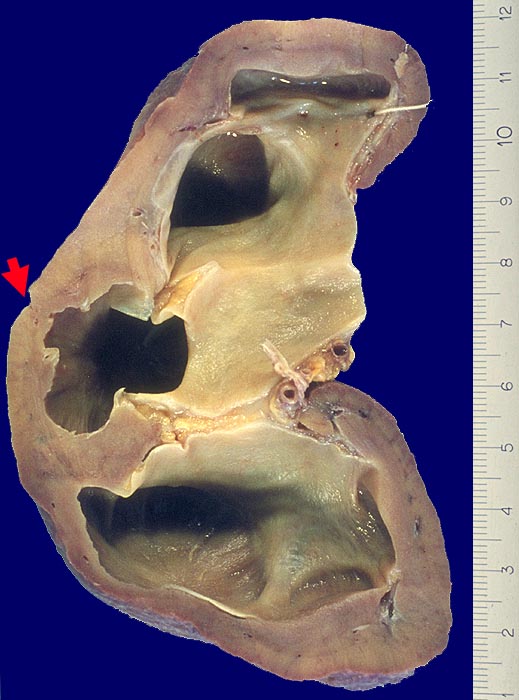

Morphologie: Die Nieren sind mehr oder weniger stark verkleinert. Die Oberfläche ist durch breitbasige und U-förmige narbige Einziehungen über dilatierten oder deformierten Nierenkelchen grob gebuckelt. Die Narben sind verschieden gross und aufgrund der starken Vaskularisation rot gefärbt. (Vaskuläre Narben sind dagegen weiss und scharf begrenzt). Das Endstadium bildet eine fein granulierte Schrumpfniere (=totale pyelonephritische Narbenniere). Die Mark-Rindengrenze ist verwaschen. Die Narben sind auf Schnitt keilförmig und reichen mit der Keilspitze bis ans Nierenbecken. Die Nierenbeckenschleimhaut ist stark verdickt und eventuell gerötet. Papillennekrosen sind besonders bei Diabetikern und Analgetikanephropathie häufig.